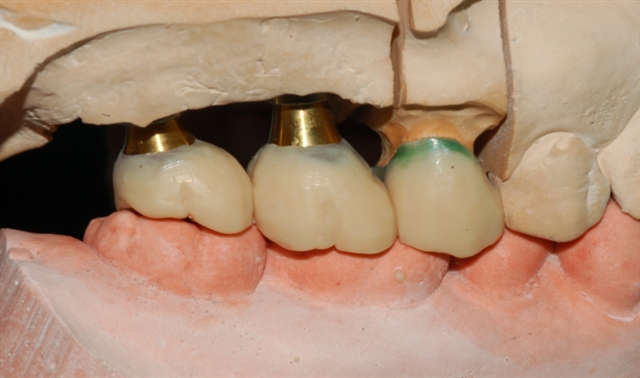

种植体上部结构加工过程